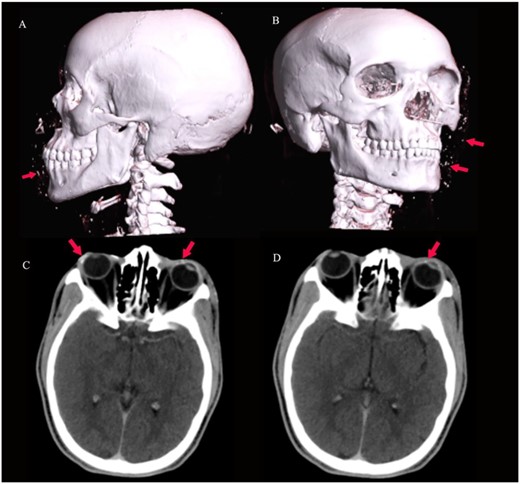

3D virtual reconstruction images (A and B) show multiple radio-opaque foreign bodies in the subcutaneous tissue of the face, as shown by arrows. Axial CT of the brain (C and D) at the level of the orbits shows conjunctival foreign bodies (shrapnel), as shown by arrows.